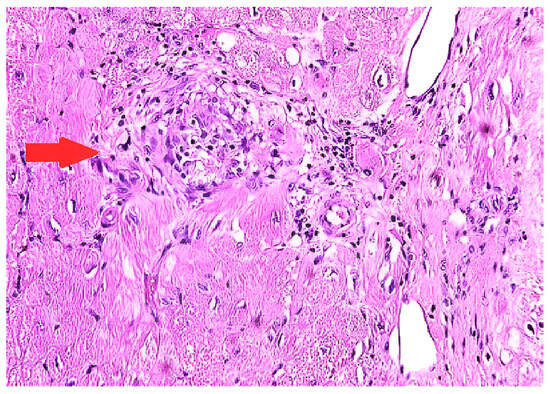

5.3. Endomyocardial Biopsy (EMB)